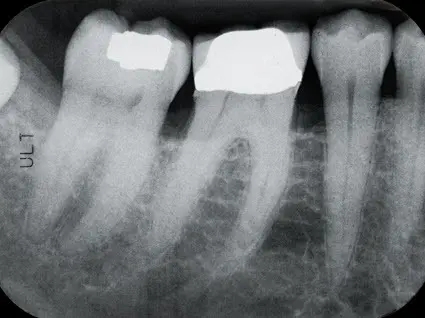

위 엑스레이 사진을 보시면 신경치료가 되어있지 않은데도 크라운이 씌워진 모습을 보실 수 있습니다 .이런 치료도 가능합니다. 상황에 따라 다르게 되죠. 참고로 신경치료가 되어있는 치아는 엑스레이 사진을 찍었을때 신경부분이 검은색이 아닌 흰색으로 보이게 됩니다 (출처: https://www.dentistinpicorivera.com/)